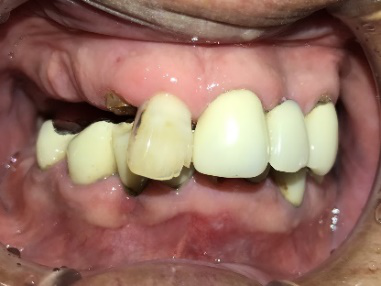

男性Kさん 50代(インプラント)

歯がグラグラするところ、むし歯のところ、しみるところ、被せ物がとれたところ、歯茎が腫れて血が出るところ、歯が抜けているところがある。すべて治したい。

治療内容

残っている歯を抜歯し、上下インプラント治療をしました。

所感

歯周病が進行している歯、むし歯が進行している歯がほとんどで、レントゲンを撮り、詳しく診てみると、ほとんどの歯を保存することができないことがわかりました。抜歯後は、入れ歯かインプラントの方法があります。治療開始前に患者さんに詳しく現状を説明し、治療法についてじっくり相談しました。自分の歯と同じような感覚で食事できるインプラント治療を選択されました。治療後、表情がとても明るくなり、口元がとても自然で10歳以上若返ったように感じました。「時間はかかりましたが、インプラントにして本当に良かったです!」と素晴らしい笑顔でお話ししてくださいました。

上顎:¥3,280,000(税込)

下顎:¥3,280,000(税込)